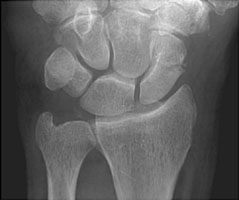

- Click on the image for a larger versionBPA radiograph of the wrist. This demonstrates a scaphoid waist fracture.